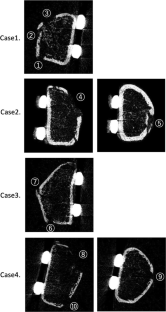

A total of 10 fracture sites identified from four patients with a distal radius fracture who underwent internal fixation with a volar locking plate (mean age 68.8 years, all women) were investigated. HR-pQCT was performed within a week (baseline) 4, 12, and 24 weeks after fracture. Rectangular region of interest (ROI) was established in the fracture site, inner callus, and external callus area, and the changes in bone mineral density (BMD) in each region were analyzed.

Fig. 2